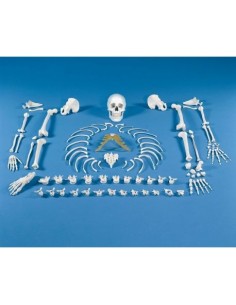

Découvrez le monde de l'anatomie avec des modèles anatomiques de précision

Bienvenue sur Tuttoanatomia.it, le portail de référence en Italie pour l'achat de modèles anatomiques, de posters, de lits portables, de simulateurs médicaux et de littérature spécialisée. Grâce à nos modèles anatomiques de pointe de 3B Scientific et Erler Zimmer, nous offrons une expérience d'apprentissage inégalée.

Des modèles anatomiques détaillés pour tous les besoins

Du crâne en 22 parties à verrouillage magnétique aux modèles de colonne vertébrale, des modèles d'articulation aux modèles de cœur, chaque pièce de notre collection est conçue pour une immersion totale dans l'étude de l'anatomie humaine. Nos modèles, réalisés à partir de scans d'os réels, garantissent une expérience tactile authentique et une fidélité de poids presque identique aux originaux.

Des outils pédagogiques innovants pour l'enseignement et la pratique de la médecine

Indispensables aux étudiants comme aux professionnels, nos modèles anatomiques sont des outils pédagogiques qui permettent d'observer les structures anatomiques avec précision, en évitant les dissections ou les études invasives. Ils sont également utiles pour expliquer les pathologies aux patients, ce qui rend la communication plus efficace et permet de gagner un temps précieux.